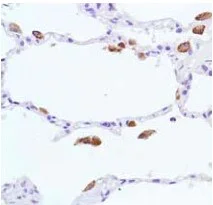

ab133543 staining liver arginase in paraffin embedded human hepatocellular cancer tissue sections by Immunohistochemistry.

Heat mediated antigen retrieval was performed using ab93684 (Tris/EDTA buffer, pH 9.0).

Samples were incubated with primary antibody at 1 : 2000 dilution (0.13 μg/ml).

A ready to use Goat anti-rabbit IgG H&L (HRP) was used as the secondary antibody.

Hematoxylin was used as a counterstain.

Cytoplasmic and nuclear staining on human hepatocellular cancer.